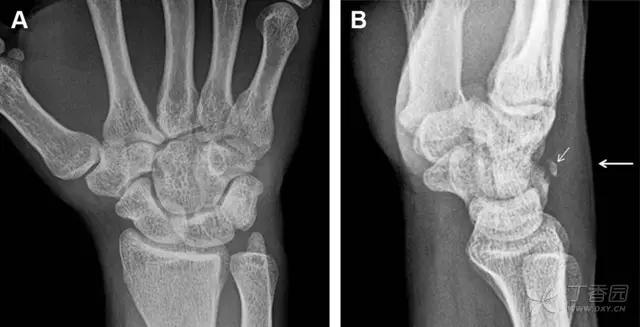

30 桡骨远端骨折

常规进行前后位、侧位、斜位 X 线检查,对于大多数桡骨远端骨折来说不容易漏诊;但是对于无移位的骨折,特别是桡骨茎突骨折,容易漏诊。桡骨茎突骨折是一斜行的骨折,常累及关节面,常发生于轴向应力或直接打击。

图 1 57 岁女性,摔倒后手掌撑地,桡骨茎突压痛。(A~C)前后位、斜位、侧位片示软组织肿胀(*)和发丝样骨折(白色箭头);(D~F)2 周后,前后位、斜位、侧位片示骨折线显明,由于新骨痂沉积而呈现透亮线与硬化线并存;(G~I)另一患者,桡骨茎突骨折在前后位及侧位片上显示不明显,而在斜位片显示更清楚